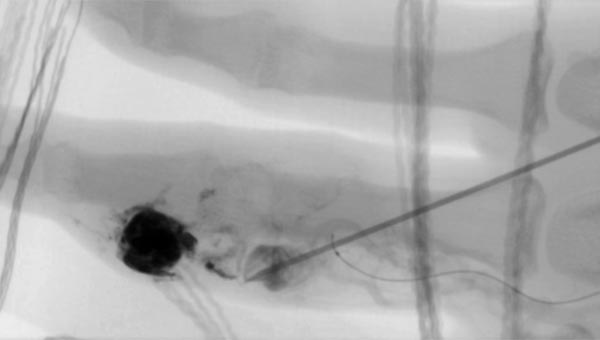

The nidus of the AVM in a magnified target image of the D III in digital subtraction angiography shows significant increase in size compared to the old angiographies (not shown). DSA images after transarterial antegrade puncture of the brachial artery with hypervascularized AVM of the middle and distal phalanx.

Fluoroscopic view of the puncture needle at the start of direct percutaneous embolization therapy of the finger with a liquid embolic agent (EVOH). The microcatheter which has been advanced to the nidus is additionally visible.

Fluoroscopic control after successful nidus embolization of the AVM. The transarterially inserted microcatheter was left in place during percutaneous embolization as a landmark for the feeding digitalis propria artery. In addition, radiopaque markers are displayed by gauze placed on the skin.